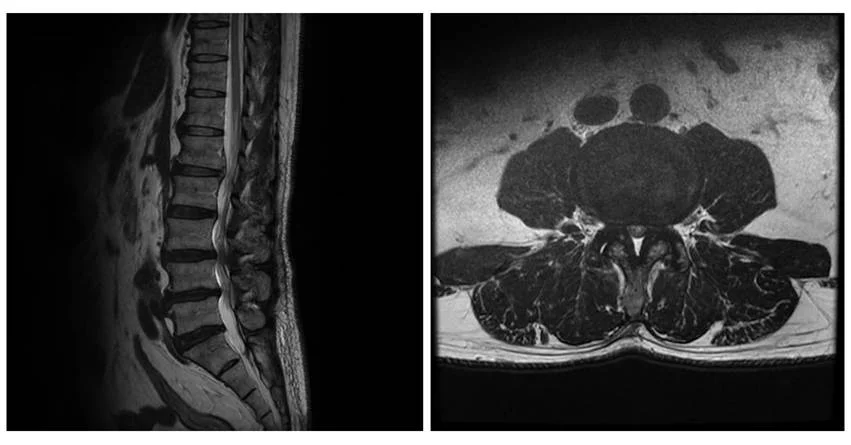

椎管狭窄症是指,脊椎内部神经通道(即“椎管”)变窄的状态。

椎管的狭窄可能出现在脊椎的任何部位,但最常见的部位是:

- 腰部(腰椎椎管狭窄症)

- 颈部(颈椎椎管狭窄症)

椎管狭窄症的主要原因是由于年龄增长引起的椎间盘退行性病变,以及骨骼与韧带的增生与变形。

随着年龄的增长,椎间盘开始退化。退化加剧时,椎间盘的纤维环可能出现裂缝,髓核突出,形成椎间盘突出。

当髓核压迫椎管时,就可能发展为脊柱管狭窄症。

此外,随着退行性病变加剧,椎间盘逐渐失去水分,变薄,缓冲能力下降,脊椎的稳定性变差,可能出现骨错位(滑脱),进一步导致椎管变窄,形成椎管狭窄症。